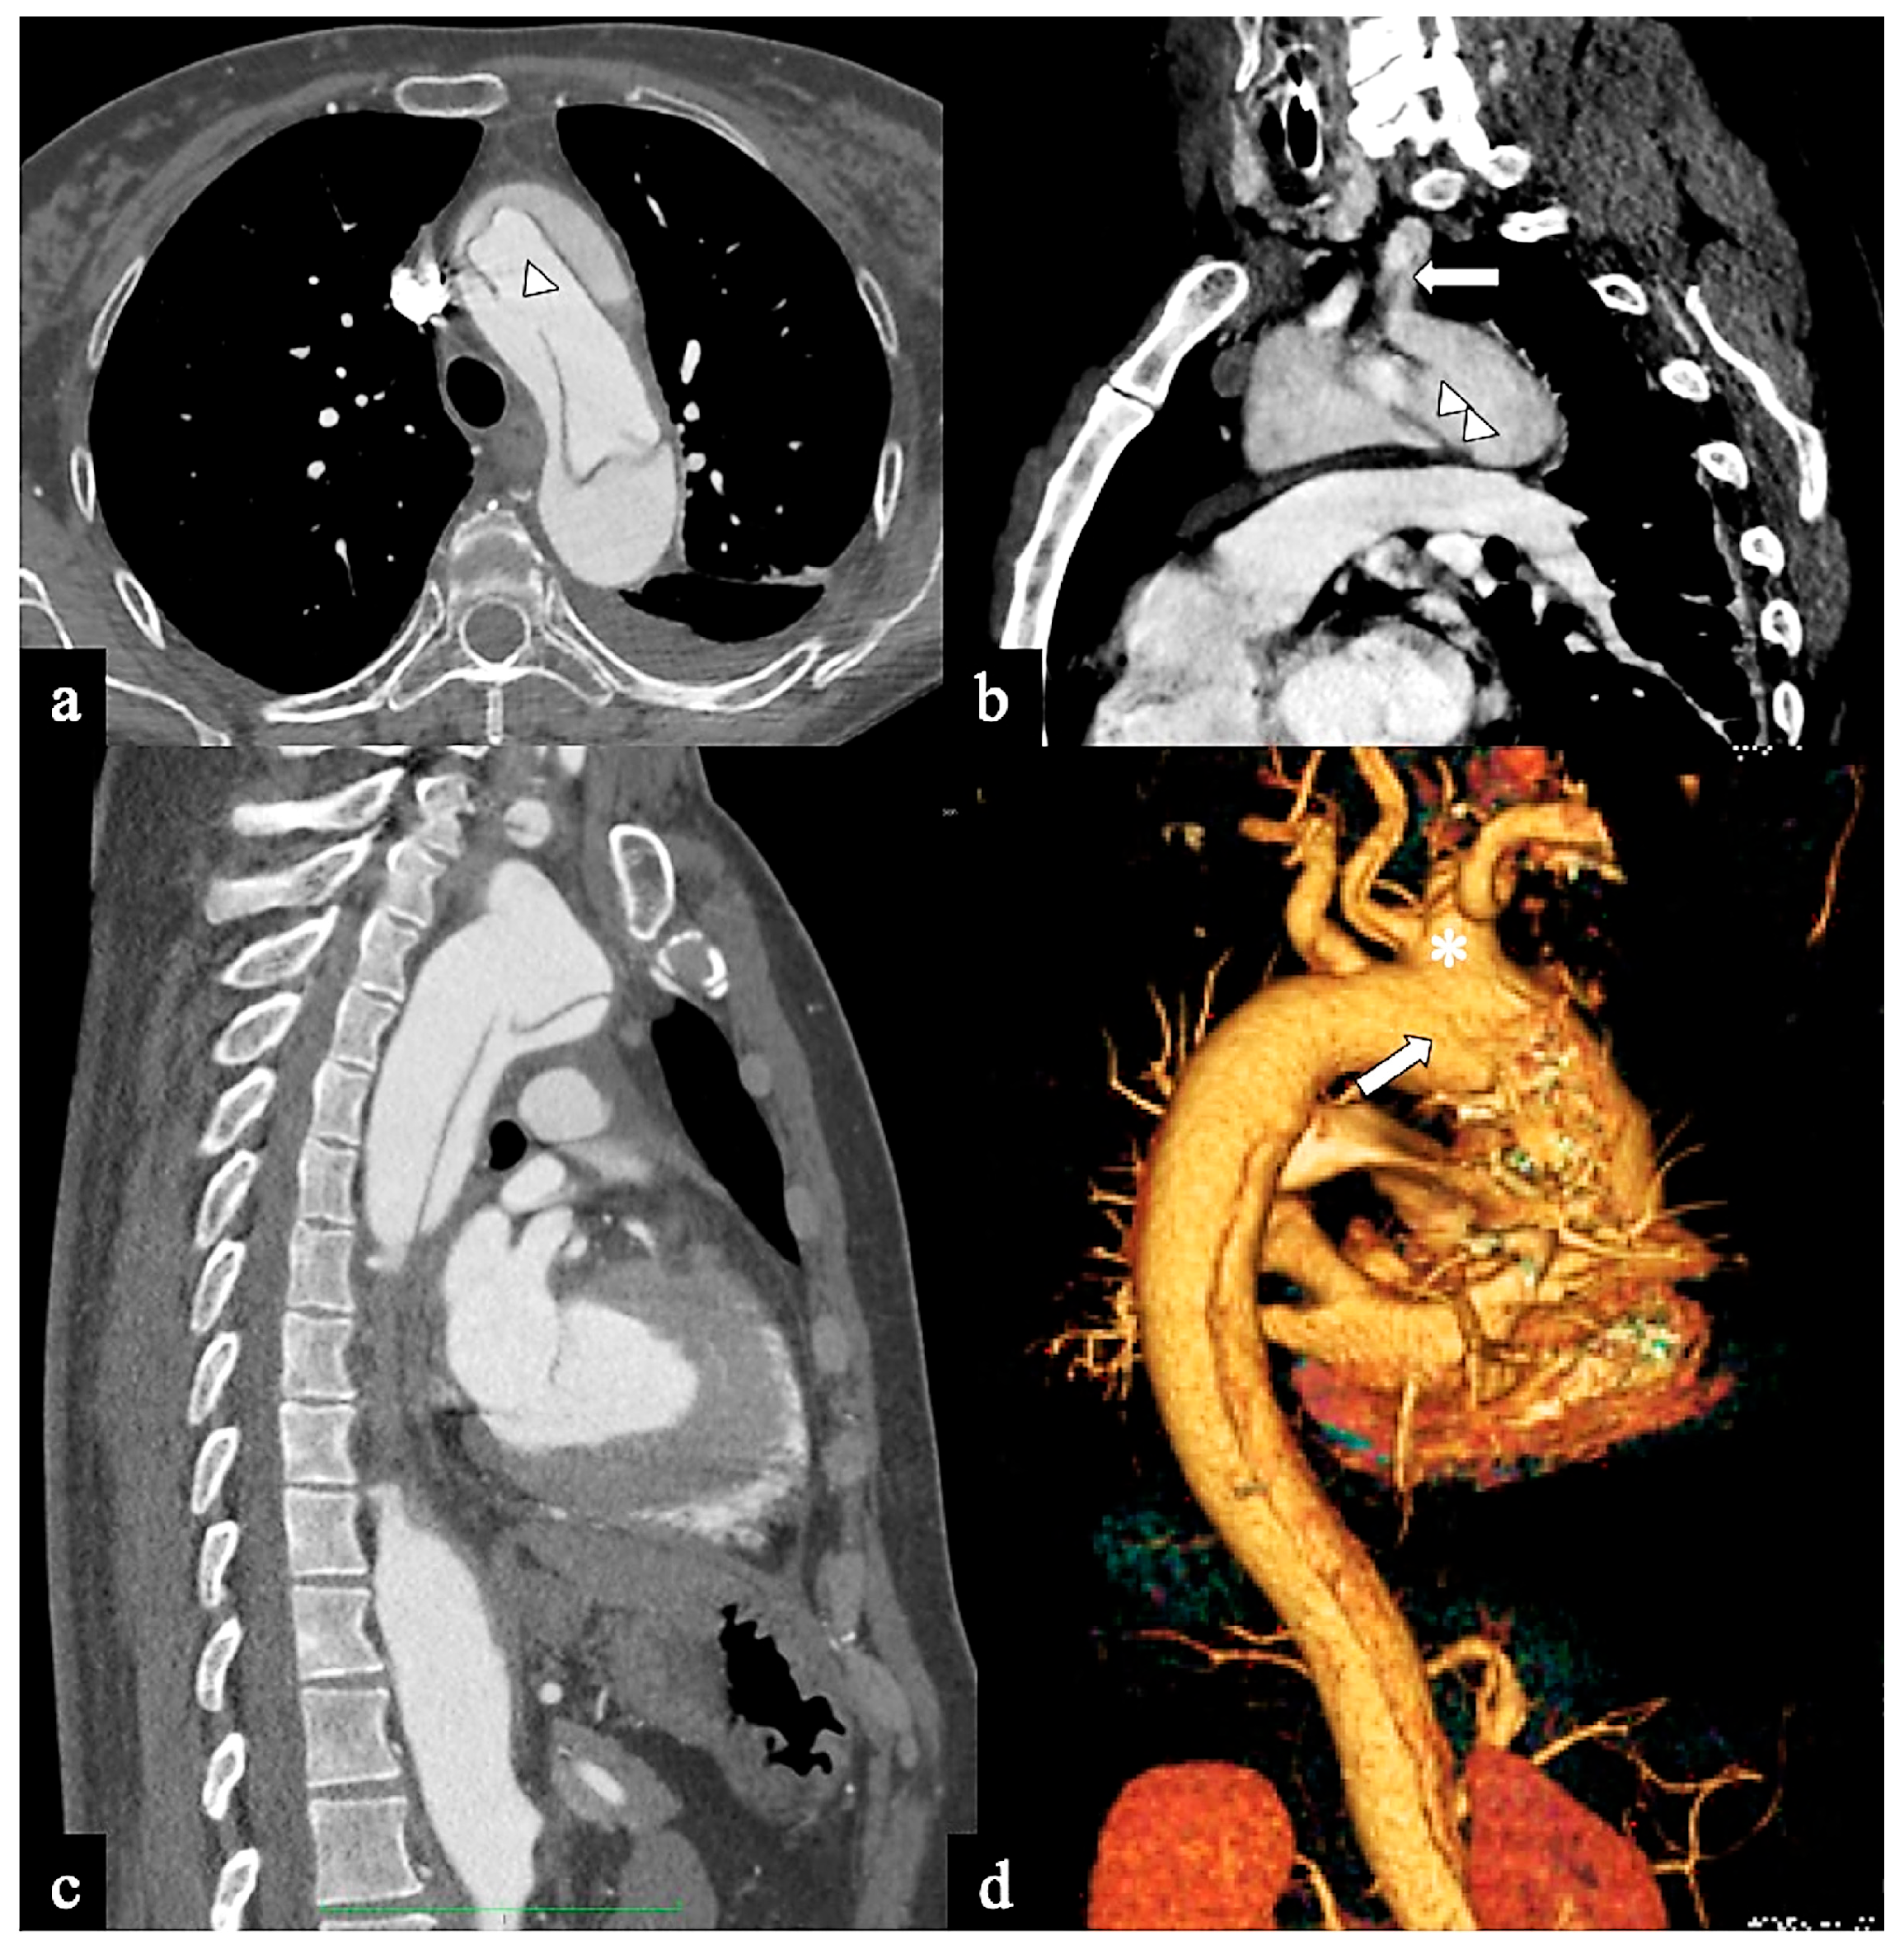

- In Configuration 3 (Arch entry), the primary ET is situated within the aortic arch, and the flap extends into the DTA without affecting the ascending aorta [38]. This Configuration 3 occurred in 7 (19%) patients (Figure 5a,b). This AD configuration was already described as proximal type B dissection according to 2010 AHA guidelines [7] and recently reported as arch B group AD from IRAD [38] and as non-A non-B acute AD with entry tear in the aortic arch [39,40]. In this configuration, the ET was often located in the greater curvature of the arch (4/6), while in one case (1/7) its location was not clearly identified. In total, 4/7 of these patients underwent hybrid and 2/7 surgical therapy.